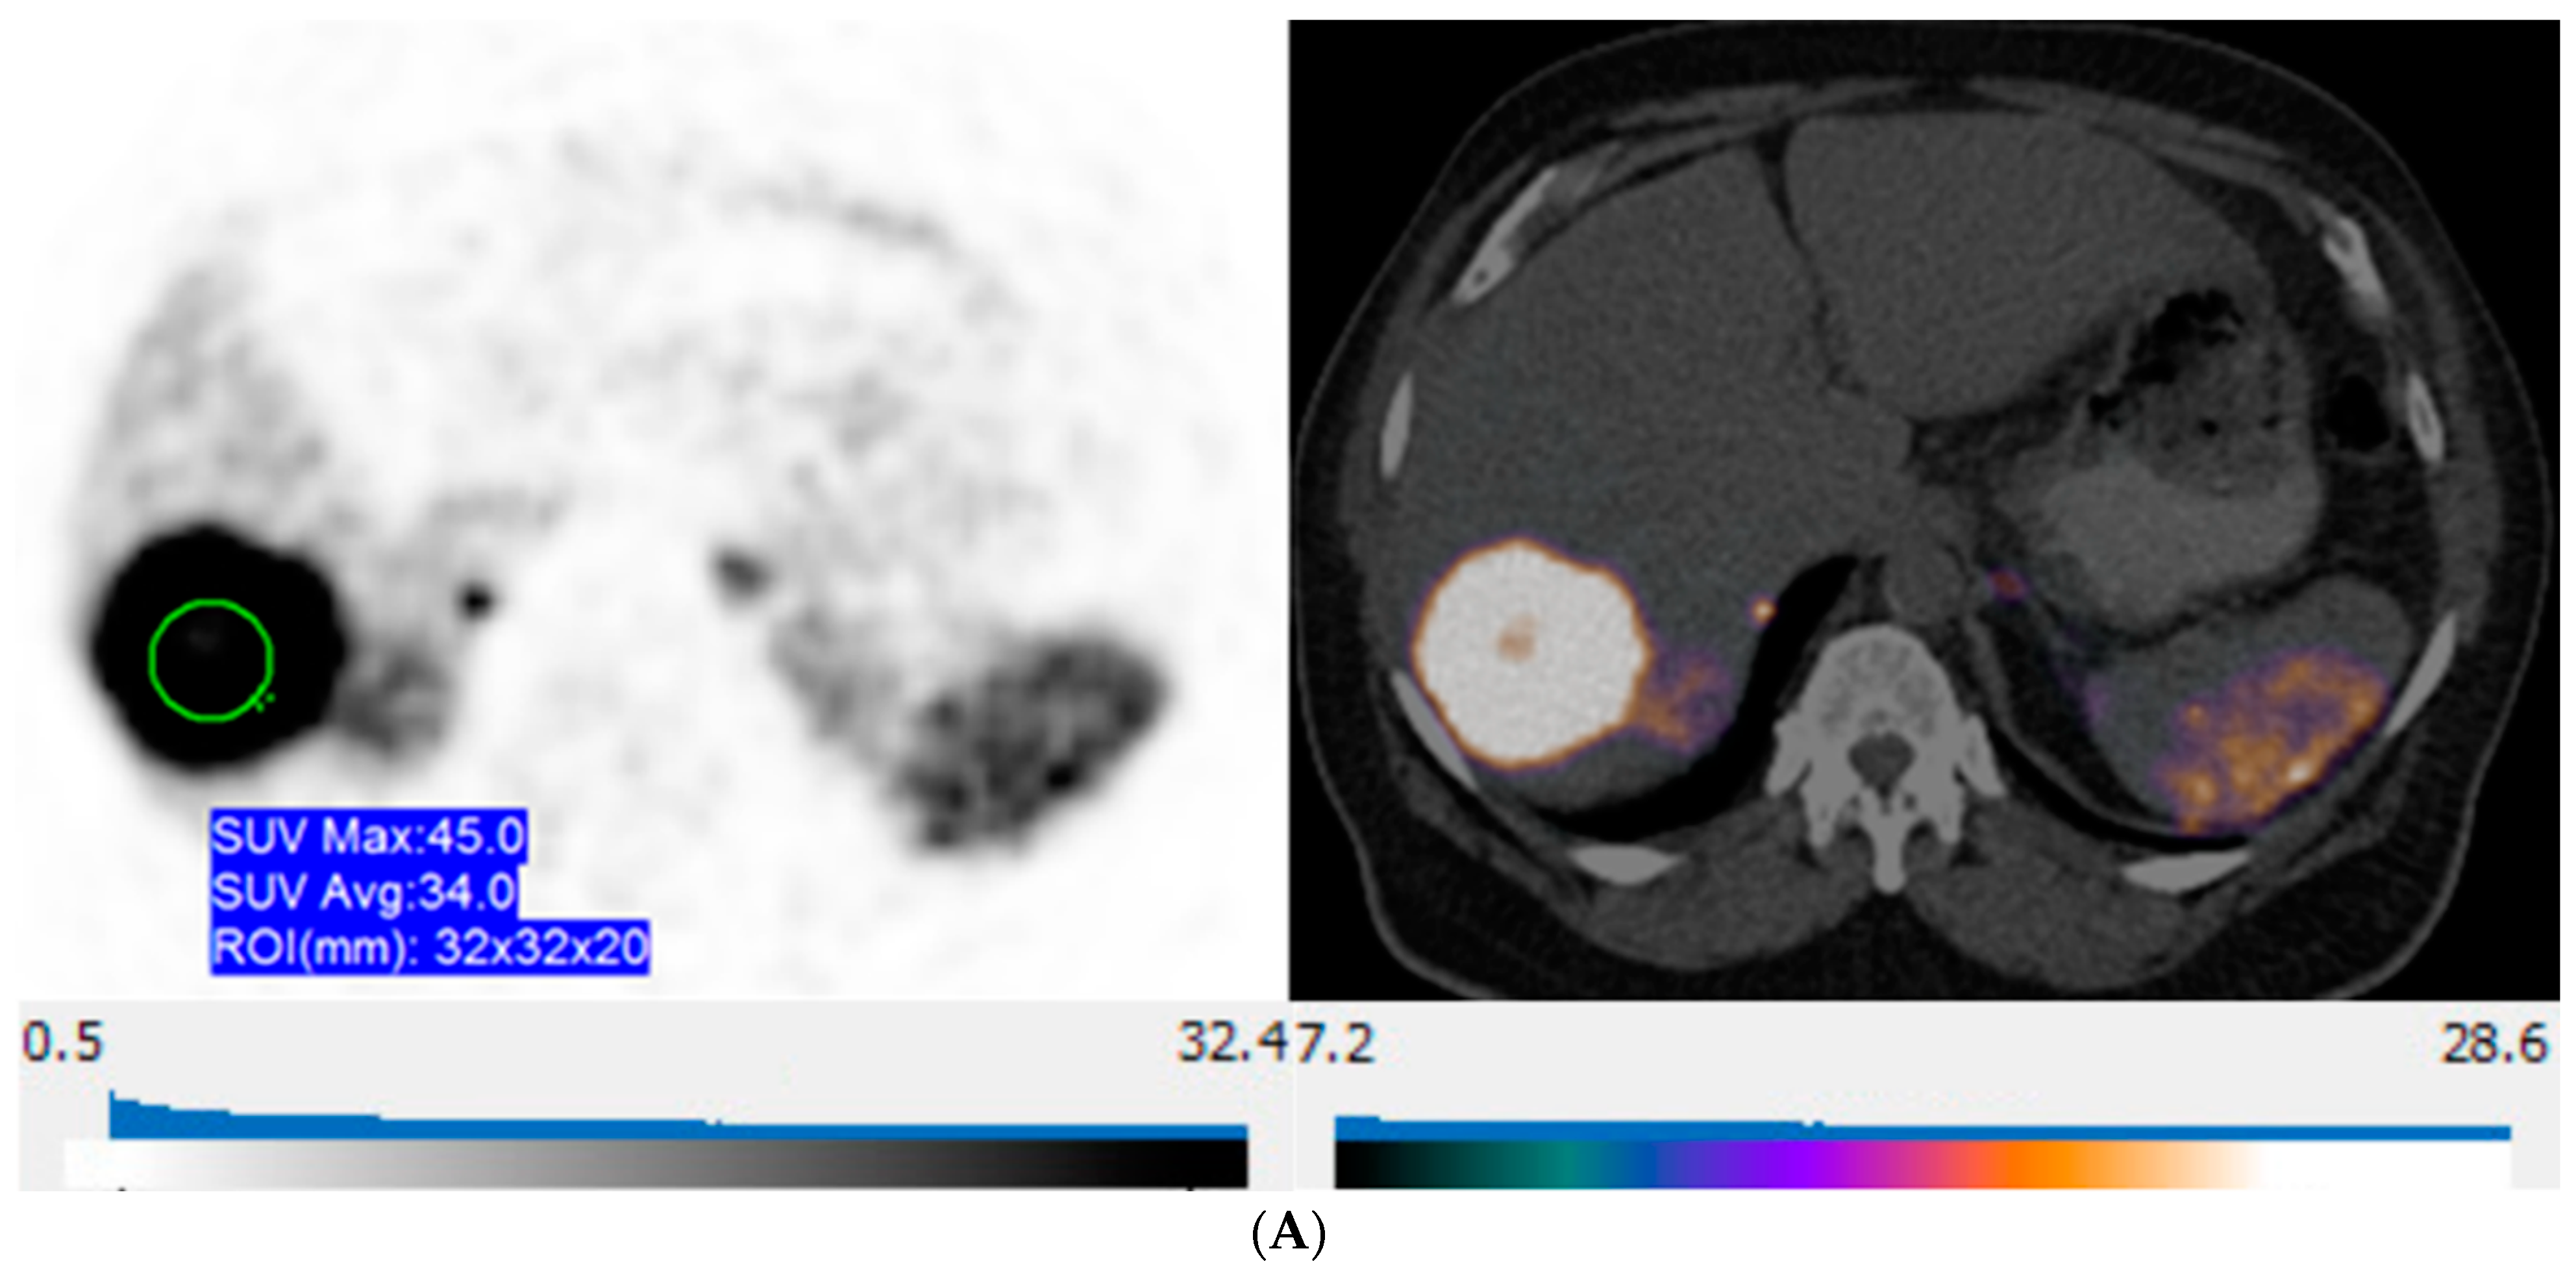

| SUV metrics | ||

| Maximal SUVmax | Mean ± SD (range) | 37.7 ± 26.7 (5.5, 146.6) |

| Minimal SUVmax | Mean ± SD (range) | 19.7 ± 11.2 (4.4, 54.8) |